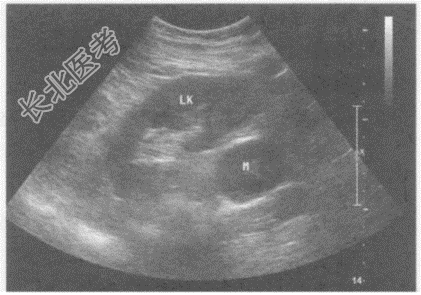

- 单项选择题临床资料:男性患者, 73岁,自述2年前体检发现左侧腹膜后肿物, 大小4.3cm×3.0cm,此后多次复查肿物大小无明显变化。

超声综合描述: 左肾下极与腹主动脉之间可见不均质低回声,与腹主动脉关系密切, 边界清晰,形态规则, 内可见形态不规则无回声,CDFI: 其内及周边均未见动静脉血流信号。见下图及彩图55。